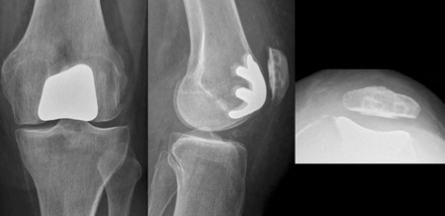

- Η αντικατάσταση (αρθροπλαστική) της επιγονατιδομηριαίας άρθρωσης είναι ένας τύπος μερικής αρθροπλαστικής γόνατος που χρησιμοποιείται για να αντικαταστήσει το φθαρμένο (αρθριτικό) επιγονατιδομηριαίο διαμέρισμα του γόνατος, δηλαδή την επιγονατίδα και τη μηριαία τροχιλία επί της οποίας ολισθαίνει καθώς το γόνατο κάμπτεται και εκτείνεται

- Για να ανακουφιστεί ο ασθενής από την προχωρημένη επιγονατιδομηριαία οστεορθρίτιδα αφαιρείται η αρθρική επιφάνεια της επιγονατίδας και αντικαθίσταται με πλαστικό και η αντίστοιχη επιφάνεια στο μηρό που ονομάζεται τροχιλία, αντικαθίσταται από μέταλλο

- Οι υπόλοιπες αρθρικές επιφάνειες του έσω και έξω διαμερίσματος του γόνατος καθώς και οι σύνδεσμοι παραμένουν ανέπαφες

- Ακτινογραφίες:

- Προσθιοπίσθια λήψη: βοηθά στην επιβεβαίωση ότι το έσω και έξω διαμέρισμα του γόνατος δεν πάσχουν από σημαντική αρθρίτιδα

- Πλάγια λήψη: Αξιολόγηση του βαθμού φθοράς του επιγονατιδομηριαίου διαμερίσματος

- Λήψη καθ’ εφαπτομένη: βοηθά στην απεικόνιση του βαθμού φθοράς μεταξύ της επιγονατίδας και του μηριαίου